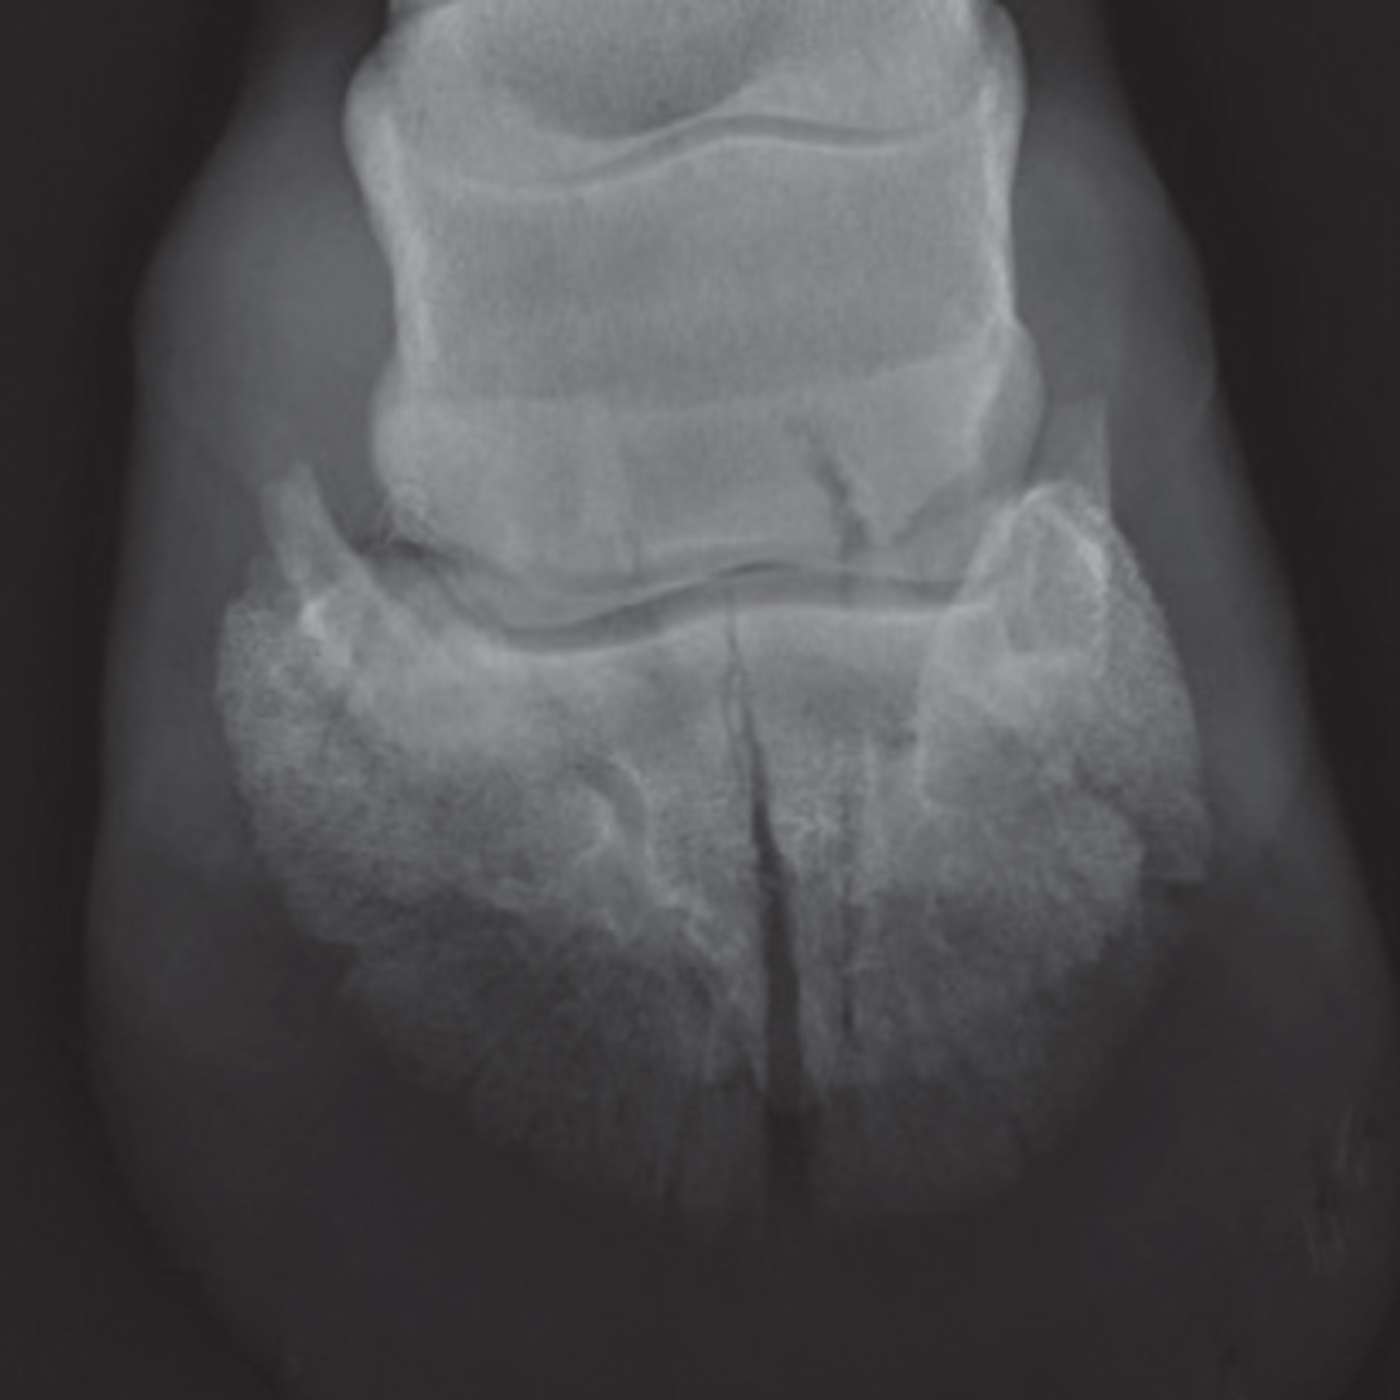

In this episode of The Hoofcare Companion, host Marc Jerram explores one of the most significant yet often misunderstood hoof injuries — pedal bone fractures. Joined by expert insights from veterinary and farriery perspectives, Marc breaks down how these fractures occur, how they’re classified, and the latest approaches to diagnosis, treatment, and rehabilitation.

Listeners will gain a clear understanding of the vital role of radiography, therapeutic shoeing, and owner management during recovery, as well as how farriers and vets can work together to support long term soundness.